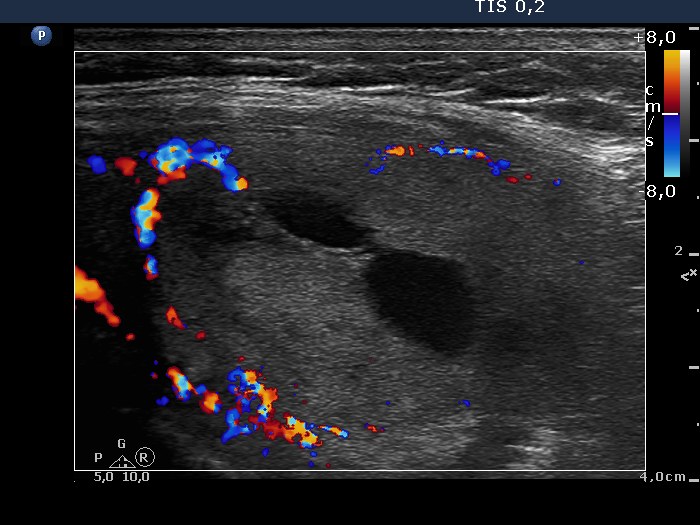

Follicular adenoma - Case 6. |

Clinical data: a 62-year old woman was presented with difficulties in swallowing.

Palpation: a nodule in the left lobe.

Functional state: euthyroidism with TSH 3.38 mIU/L.

Ultrasonography: the thyroids were echonormal. There was a moderately hypoechogenic and an echonormal lesion in the right lobe. The left lobe contained a large echonormal nodule. The nodule displayed a halo sign and perinodular blood flow and central cystic degeneration.

Cytology resulted in follicular tumor.

Histopathology disclosed follicular adenoma.